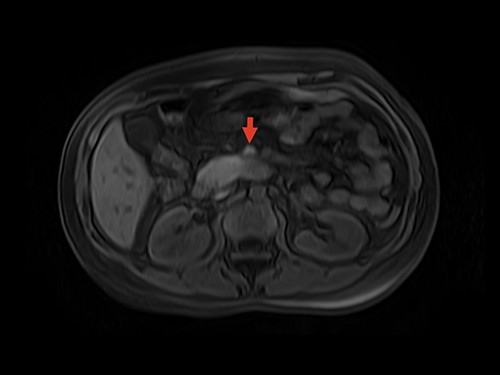

Magnetic resonance image (MRI) was performed. MVT and venous ischemia of a small bowel loop were identified (Figs 1 and 2). She underwent a diagnostic laparoscopy that showed hemorrhagic content in the pelvis and omental plastron surrounding an ischemic bowel loop. The procedure was converted and enterectomy was performed (Fig. 3).

MRI showing superior mesenteric vein thrombus. Arrow: superior mesenteric vein with thrombus inside the vein lumen.